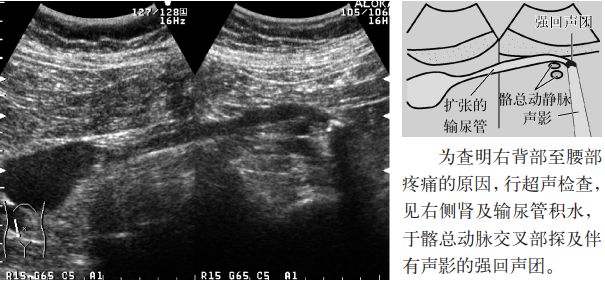

1.扩张的输尿管内探及伴有声影的高回声。

2.伴有中心部回声(central echoes,central echo complex,CEC;肾窦)分离(肾积水)。

图11 输尿管结石(髂动脉交叉部)

1.大部分输尿管结石是肾结石掉入输尿管,大多数嵌顿于生理性三个狭窄部位:①肾盂输尿管移行部;②输尿管与髂总动脉的交叉部;③输尿管膀胱移行部,引起输尿管扩张(输尿管积水),几乎所有的病例均导致肾积水。